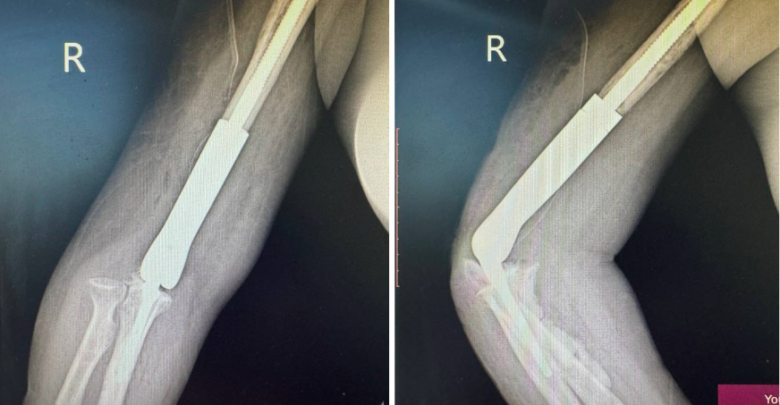

Уг мэс засал нь авто ослын дараах атгаалын чөмөгт ясны доод хэсэг бяцарч, үйрмэг мэт болон хугарч, эргэн сэргэшгүй болж дутмагшил үүссэн (10см орчим) ясыг орлуулах, үеийг орлуулсан, нийлмэл тохойн хиймэл үе бүхий имплантыг суурилуулан гарын хөдөлгөөнийг бүрэн сэргээж, амьдарлын чанарыг сайжруулах мэс засал эмчилгээ юм.

Тус мэс заслын баг бүрэлдэхүүнд ГССҮТ-ийн Гар сарвууны мэс заслын тасгийн эрхлэгч Л.Нанжид болон их эмч Ж.Баярмагнай, Т.Баян-Өлзий, Ц.Санжаасүрэн, мэдээгүйжүүлэгийн эмч Г.Ариунболд, сувилагч Т.Гантулга, Б.Базаррагчаа, Г.Ганцэцэг нар оролцсон байна. Эмчлүүлэгчийн биеийн байдал тогтвортой байгаа бөгөөд мэс засал эмчилгээний дараах нөхөн сэргээх эмчилгээнд хамрагдаж байна.